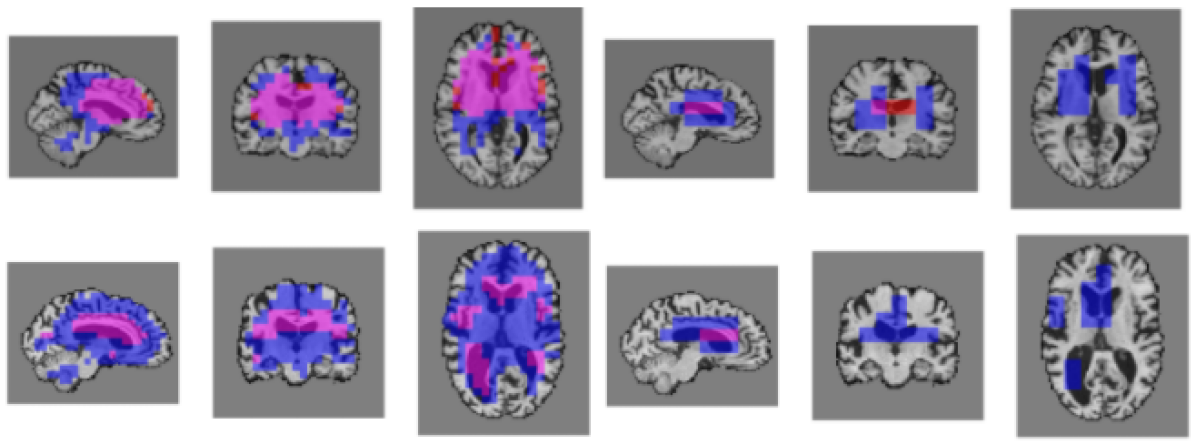

Refer to caption

Fig. 4: Saliency visualization maps produced by the model for two different subjects. Three left panels show saliency maps for the first attention module and the rightmost three panels correspond to the second module. Red colors denote voxels relevant for AD classification, blue voxels for age prediction, and purple colors show the region of overlap of voxels relevant for each task. Top row uses a threshold of 2 standard deviations above mean attention, while the bottom row uses a threshold of 1 std above the mean.

We visualize region saliency using the attention masks (normalized attention scores) produced by the attention modules. We upsample these masks to the original size of our scan using nearest neighbor interpolation and mask out artifacts by multiplying by the binary brain mask. For analysis, we apply binary thresholding based on the mean attention value. Figure 4 shows examples of saliency maps produced by our model at different thresholds. We note that saliency maps produced by the network differ by subject and are based on relevant areas used to classify each scan.

where AD and AGE are binary (thresholded) importance regions. Results are presented in Table 1. As the σ𝜎\sigma threshold decreases, there is a greater difference in overlap between attention modules. For σ=1𝜎1\sigma=1 there is a 0.52 overlap for the first attention module compared to only 0.1 for the subsequent module. This implies that feature complexity plays a crucial role in common region saliency between tasks. Visually, this can also be seen in Figure 4. Age prediction focuses on a much larger region of features compared to AD classification which focuses mainly on the ventricles. This may explain why more complex age prediction models tend to more accurately predict age in diseased subjects. We also observed little difference between average scores for subjects with AD versus healthy controls.